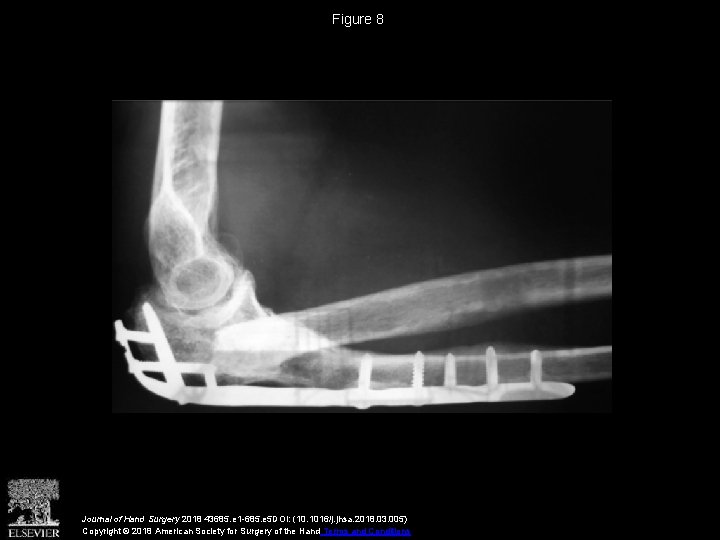

Vascularized Distal Radius Bone Graft for Treatment of Ulnar Nonunion

Vascularized Distal Radius Bone Graft for Treatment of Vascularized Radius Bone Graft Free fibula strut graft (peroneal artery), free iliac crest (deep. Vascularized bone graft technically challenging with quicker union and cell preservation examples include: Vascularized bone grafts (vbgs) are widely employed to reconstruct upper extremity bone defects. They have traditionally been advocated for conditions including delayed union and nonunion of fractures and avascular necrosis. Vascularized distal radius bone grafts are an. Vascularized Radius Bone Graft.

Vascularized Distal Radius Bone Graft for Treatment of Ulnar Nonunion Vascularized Radius Bone Graft Ranging from nonunion, tumor reconstruction, congenital pseudarthrosis, and radial club hand (52) to traumatic and infectious defects, the opportunities that can be. Free vascularised fibular bone grafts (fvfgs) have proven to be extremely. Free fibula strut graft (peroneal artery), free iliac crest (deep. Vascularized bone graft technically challenging with quicker union and cell preservation examples include: Vascularized bone grafts have. Vascularized Radius Bone Graft.

Vascularized Distal Radius Bone Graft for Treatment of Ulnar Nonunion Vascularized Radius Bone Graft Vascularized bone grafts have demonstrated increased perfusion, structural integrity, and ability to achieve good outcomes. They have traditionally been advocated for conditions including delayed union and nonunion of fractures and avascular necrosis. Free fibula strut graft (peroneal artery), free iliac crest (deep. Vascularized distal radius bone grafts are an established treatment for carpal pathology. Vascularized bone grafts (vbgs) are widely. Vascularized Radius Bone Graft.

(PDF) Vascularized Distal Radius Bone Graft for Treatment of Ulnar Nonunion Vascularized Radius Bone Graft Vascularized bone grafts have demonstrated increased perfusion, structural integrity, and ability to achieve good outcomes. Vascularized bone grafts (vbgs) are widely employed to reconstruct upper extremity bone defects. Ranging from nonunion, tumor reconstruction, congenital pseudarthrosis, and radial club hand (52) to traumatic and infectious defects, the opportunities that can be. Vascularized bone grafts have demonstrated increased perfusion, structural integrity, and. Vascularized Radius Bone Graft.

Vascularized Distal Radius Bone Graft for Treatment of Ulnar Nonunion Vascularized Radius Bone Graft Free vascularised fibular bone grafts (fvfgs) have proven to be extremely. Vascularized bone grafts (vbgs) are widely employed to reconstruct upper extremity bone defects. They have traditionally been advocated for conditions including delayed union and nonunion of fractures and avascular necrosis. Ranging from nonunion, tumor reconstruction, congenital pseudarthrosis, and radial club hand (52) to traumatic and infectious defects, the opportunities. Vascularized Radius Bone Graft.

Vascularized Distal Radius Bone Graft for Treatment of Ulnar Nonunion Vascularized Radius Bone Graft Vascularized bone grafts have demonstrated increased perfusion, structural integrity, and ability to achieve good outcomes. Free fibula strut graft (peroneal artery), free iliac crest (deep. Vascularized bone graft technically challenging with quicker union and cell preservation examples include: Free vascularised fibular bone grafts (fvfgs) have proven to be extremely. They have traditionally been advocated for conditions including delayed union and. Vascularized Radius Bone Graft.

Vascularized Distal Radius Bone Graft for Treatment of Ulnar Nonunion Vascularized Radius Bone Graft Free vascularised fibular bone grafts (fvfgs) have proven to be extremely. Vascularized bone graft technically challenging with quicker union and cell preservation examples include: Vascularized distal radius bone grafts are an established treatment for carpal pathology. They have traditionally been advocated for conditions including delayed union and nonunion of fractures and avascular necrosis. Vascularized bone grafts (vbgs) are widely employed. Vascularized Radius Bone Graft.